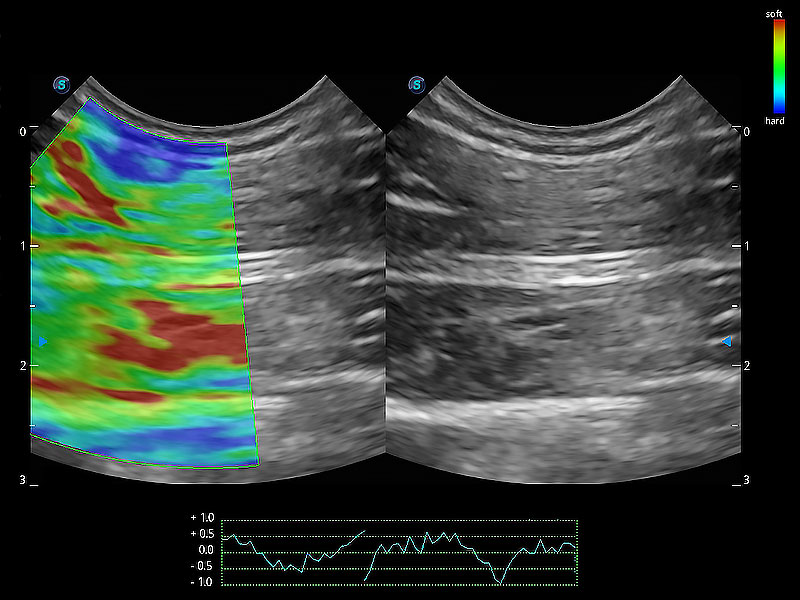

操作簡便,無需高頻度外力作用即可真實反映組織的形變,快速評估腫瘤良惡性。